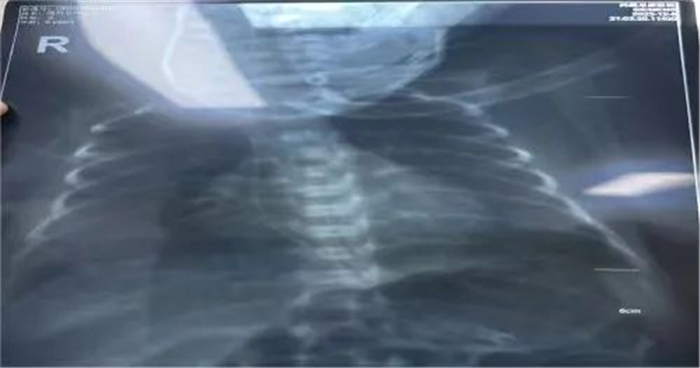

接到护理会诊通知后,我院静疗团队(IVTEAM)高度重视,认真评估患儿情况,来到科室映入眼帘的是温箱里四肢仅有拇指粗细,血管更是细如发丝的早产宝宝,了解到普通留置针穿刺实属不易,但置入PICC更是难上加难,对于我们静疗团队来说是无疑是一个巨大的挑战。在ICU任周行护士长的指导下,静疗学组组长韩晓倩、邓倩雯准备好物品,代金丽护士长小心翼翼地为宝宝摆好体位,大家一起做好基本生命支持及保暖工作,充分评估血管情况后,组长韩晓倩最终选择经右上肢贵要静脉进针,凭借过硬的穿刺技术,穿刺时一针见血,随后送管、撤导丝、固定一气呵成,经X线定位确定 PICC 导管尖端位置良好,成功了,大家终于松了一口气!